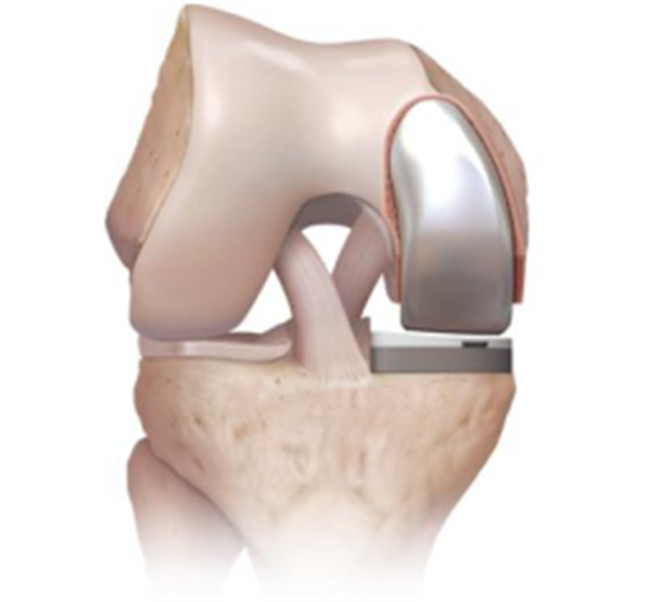

對(duì)于全膝關(guān)節(jié)置換術(shù)而言,膝關(guān)節(jié)單髁置換術(shù)是相對(duì)微創(chuàng)手術(shù),精準(zhǔn)置換病損部位,用以替代膝關(guān)節(jié)股、脛關(guān)節(jié)損壞的軟骨表面和半月板,被稱為膝關(guān)節(jié)置換中的“補(bǔ)牙技術(shù)”,不需要去除前后交叉韌帶,最大限度保留病人的本體感覺(jué)和關(guān)節(jié)功能,實(shí)現(xiàn)膝關(guān)節(jié)置換手術(shù)的生理性重建。膝關(guān)節(jié)單髁置換手術(shù)具有損傷小、術(shù)后恢復(fù)快、手術(shù)外表美觀和住院時(shí)間短等優(yōu)點(diǎn),是治療膝關(guān)節(jié)骨關(guān)節(jié)炎的理想辦法。目前,單髁置換技術(shù)是關(guān)節(jié)外科發(fā)展方向之一,隨著手術(shù)器械的發(fā)展和認(rèn)識(shí)水平的提高,單髁置換術(shù)在臨床將會(huì)擁有廣泛的應(yīng)用前景。

羅軍主任表示:膝關(guān)節(jié)單髁置換術(shù)(unicompartmental kneearthroplasty, UKA)是相對(duì)全膝關(guān)節(jié)置換術(shù)而言的一種新型微創(chuàng)手術(shù),切口僅為原來(lái)的一半,且能最大限度地保留患者正常的關(guān)節(jié)部分,對(duì)患者的損傷更小,術(shù)后療效更佳,是骨性關(guān)節(jié)炎患者的一大福音。